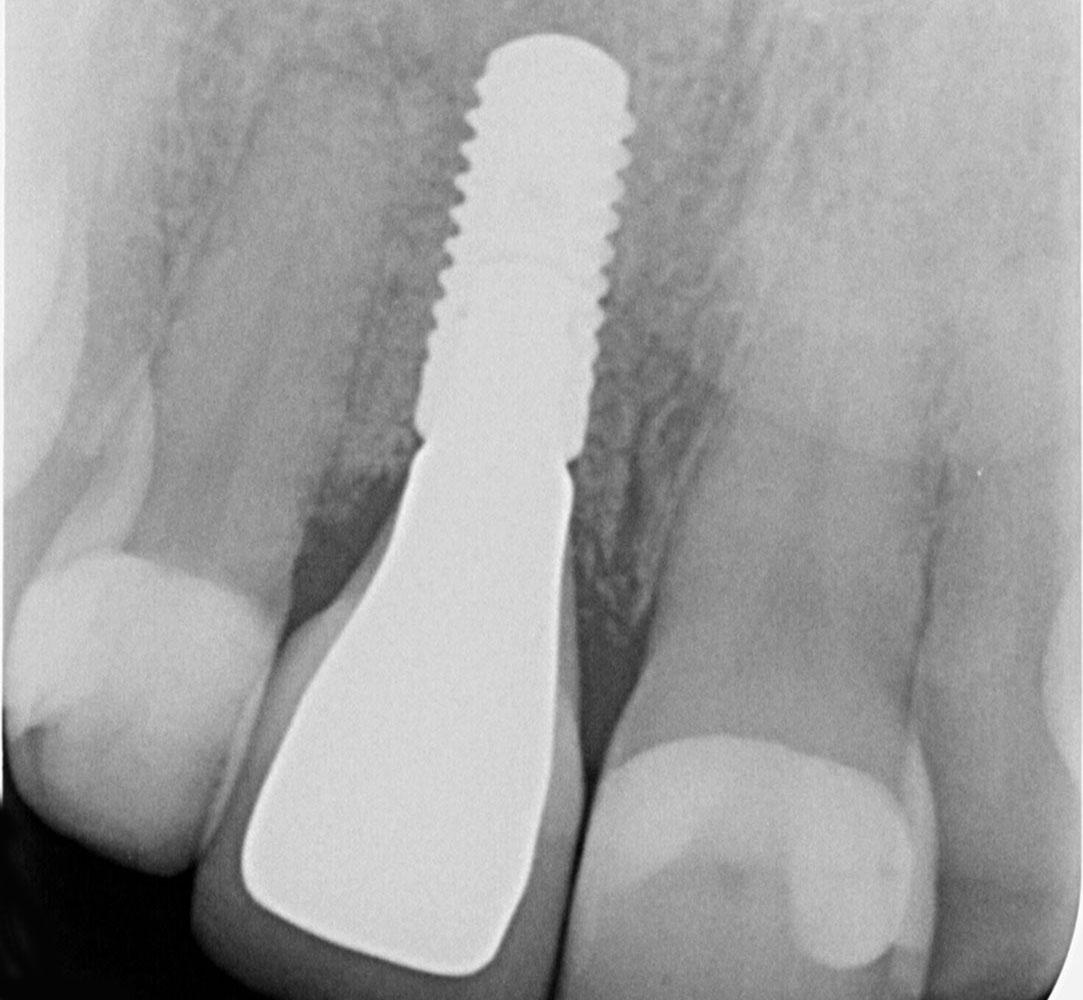

Implantate

Implantate dienen nach Zahnverlust als Wurzelersatz. Dazu wird eine Schraube aus Titan oder Keramik in den Kieferknochen eingesetzt. Nach einer Einheilphase kann das Implantat belastet werden und je nach Situation mit einer Krone, Brücke oder als Halte-Element zur Verankerung einer Prothese verwendet.